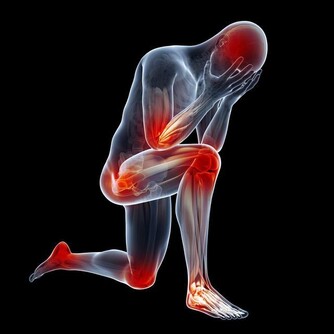

5、晚餐與高血脂症晚餐若采高蛋白,高油脂,高熱量進食方式,會刺激肝臟製造低密和極低密度脂蛋白,三酸甘油酯也容易上升,造成高血脂症。

6、晚餐與高血壓晚餐內容若偏葷食,加上睡眠時的血流速度減緩,大量血脂就會沉積在血管壁上,進而引起細小動脈更收縮,外周血管阻力增高,容易讓血壓猛然上升,也加速全身小動脈的硬化。

7、晚餐與動脈硬化與心臟病晚餐的飲食若偏高油脂,高熱量可引起膽固醇增高,並在動脈壁堆積起來,成為誘發動脈硬化和心臟病的一大原因。

此外,動脈硬化形成的另一主因,是鈣質沉積在血管內,因此晚餐的盛食,美食,飽食及太晚吃晚飯都是引發心血管疾病的其中原因。